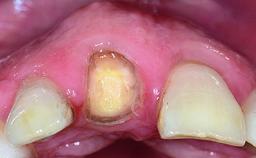

Replacement of a Failing Upper Left Central Incisor: Immediate Placement of an RC Bone Level Implant and Provisionalization

Loading Protocol Immediate

Provisional Implant-Supported Prosthesis Prosthodontic margin < 3 mm apical to mucosal margin Prosthodontic margin < 3 mm apical to mucosal margin

Soft Tissue Contour and Volume Ideal